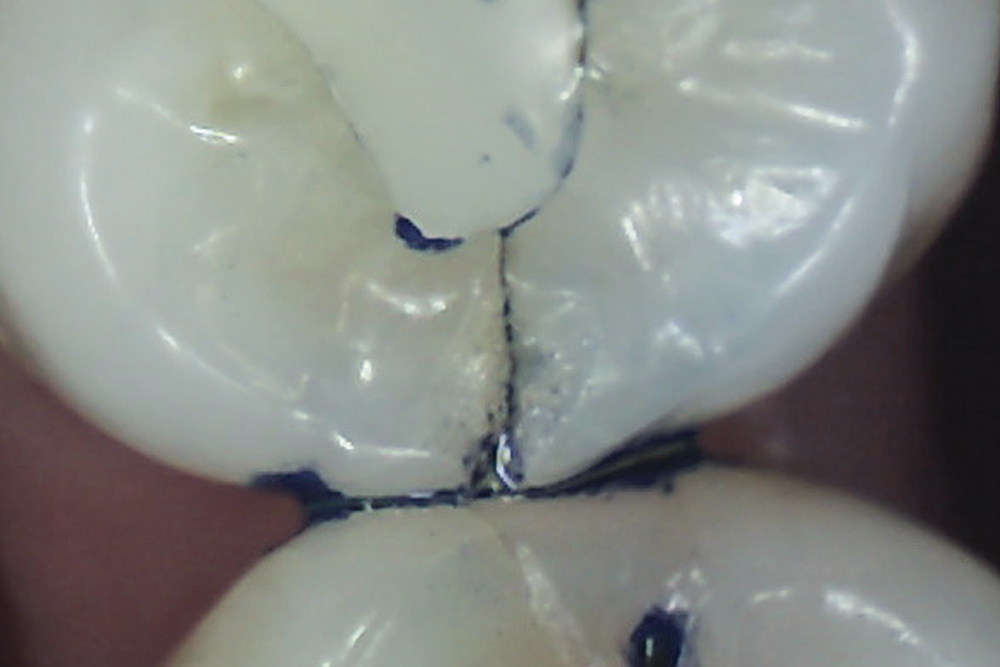

Methylene blue dye is the most commonly used dye to stain cracks because of its pooling tendency.2,3,14,16,17,23 The dye pools into the enamel and dentin cracks and the tooth is thoroughly rinsed. The resulting dark stain retained in the crack lines then helps enable cracks to be detected (Figure 4 and Figure 5). Methylene blue dye, however, also stains dental plaque, requiring the tooth surface to be cleaned with pumice or prophylaxis paste before dye application.14 The dye also can be absorbed by dentin, but any residual dye can be removed using a 10-second phosphoric acid etch.14 A comparative study of dye staining and transillumination concluded that methylene blue dye staining and transillumination performed simultaneously is the optimal crack assessment technique.23

Fig 4. Subtle asymptomatic occlusal crack (arrow) of a mandibular right second molar (occlusal view).

Fig 5. Methylene blue dye staining further revealing the occlusal extent of the crack shown in Fig 4.